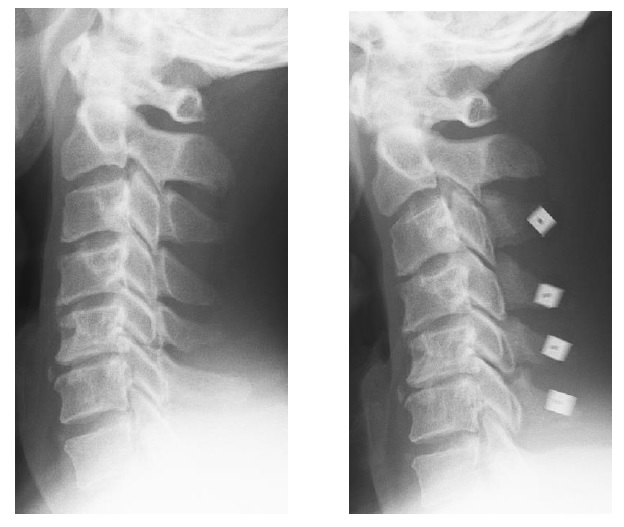

Figure 7: Simple X-ray films of a 46-year-old male with cervical spondylotic myelopathy. Before surgery (left)and after surgery (right).

figure 7